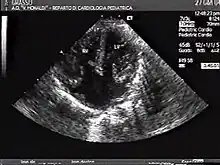

The proper development of the atrioventricular canal into its prospective components (The heart septum and associated valves) to create a clear division between the four compartments of the heart and ensure proper blood movement through the heart, are essential for proper heart function. When this process does not happen correctly, a child will develop atrioventricular canal defect which occurs in 2 out of every 10,000 births.[1] It also has a correlation with Down syndrome because 20% of children with Down syndrome have atrioventricular canal disease as well. This is a very serious condition and surgery is necessary within the first six months of life for a child.[2] Half of the children who are untreated with this condition die during their first year due to heart failure or pneumonia.[3]

Atrioventricular canal defect is a combination of abnormalities of the heart and is present at birth. There is a problem when there are holes present in the walls that separate chambers (septa), as well as when valves are incorrectly constructed. There are other names for these heart abnormalities such as endocardial cushion defects or atrioventricular septal defect[4]

Atrioventricular canal defect may be divided into partial or complete forms. In the partial form, openings between the left and right atria and improper formation of the mitral valve exist. In the complete form, there is free movement in all chambers because there is a large hole where the atria and ventricles meet, and instead of there being two valves there is one common valve.[4]